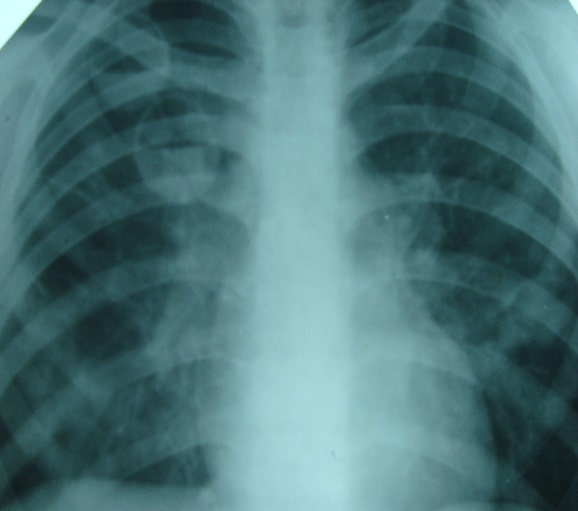

Какой синдром заболеваний легких вы видите// +затемнение// Просветление// патология корня легкого// патология легочного рисунка// патология нарушения бронхиальной

Какой патологический процесс в легких вы видите// Пневмония// Пневмоторакс// +гидропневмоторакс// Плеврит// рак легкого

Какой патологический процесс в легких вы видите// диссеминированный туберкулез легких// саркоидоз легких// +метастазы в легкие// альвеококкоз легких// эхинококкоз легких

Какой патологический процесс в легких вы видите// Пневмония// экссудативный плеврит// +осумкованный плеврит// ателектаз правого легкого// цирроз правого легкого

Какой патологический процесс в легких вы видите// пневмония левого легкого// экссудативный плеврит// осумкованный плеврит// +ателектаз левого легкого// цирроз левого легкого

Какой патологический процесс в легких вы видите// пневмония правого легкого// +пневмоторакс правого легкого// эмфизема правого легкого// ателектаз правого легкого// цирроз правого легкого

Какой патологический процесс в легких вы видите// пневмония левого легкого// пневмоторакс слева// +гидропневмоторакс слева// плеврит слева// рак левого легкого

Какой патологический процесс в легких вы видите// пневмония правого легкого// +экссудативный плеврит справа// осумкованный плеврит справа// ателектаз правого легкого// цирроз правого легкого

Какой патологический процесс в легких вы видите// пневмония левого легкого// +экссудативный плеврит слева// осумкованный плеврит слева// ателектаз левого легкого// цирроз левого легкого

Какой патологический процесс в легких вы видите// осумкованный плеврит правого легкого// +эхинококковая киста правого легкого// мезотелиома плевры правого легкого// пневмония верхней доли правого легкого// ателектаз верхней доли правого легкого

Какой патологический процесс в легких вы видите// +диссеминированный туберкулез легких// септическая пневмония// саркоидоз легких// метастазы в легкие// эхинококкоз легких

Какой патологический процесс в легких вы видите// +поликистоз легких// септическая пневмония// альвеококкоз легких// метастазы в легкие// эхинококкоз легких

Какой патологический процесс в легких вы видите// +ателектаз верхней доли правого легкого// туберкулез верхней доли правого легкого// осумкованный верхушечный плеврит// пневмония верхней доли справа// инфаркт верхней доли правого легкого

Какой патологический процесс в легких вы видите// пневмония справа// пневмоторакс правого легкого// +гидропневмоторакс справа// плеврит справа// рак правого легкого

Какой патологический процесс в легких вы видите// +абсцесс правого легкого// гангрена правого легкого// киста правого легкого// туберкулезная каверна правого легкого// периферический рак правого легкого в стадии распада